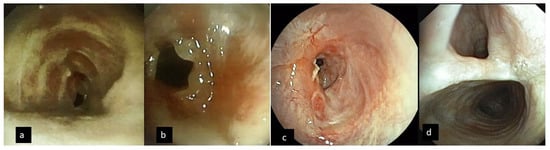

| Bronchoscopy findings | |

| Tracheal stenosis % | 84.45% ± 8.3% |

| Length of stenosis (cm) | 2.85 ± 0.9 |

| Subglottic/mid trachea | 12/11 |

| Complex or mixed/simple web | 21/2 |

| Distortion of the airway due to anterior wall cartilage fracture | 19/23 (82.6%) |

| Excessive Dynamic Airway Collapse | 5/23 (21.7%) |

| Tracheo-esophageal fistula | 2/23 (8.7%) |